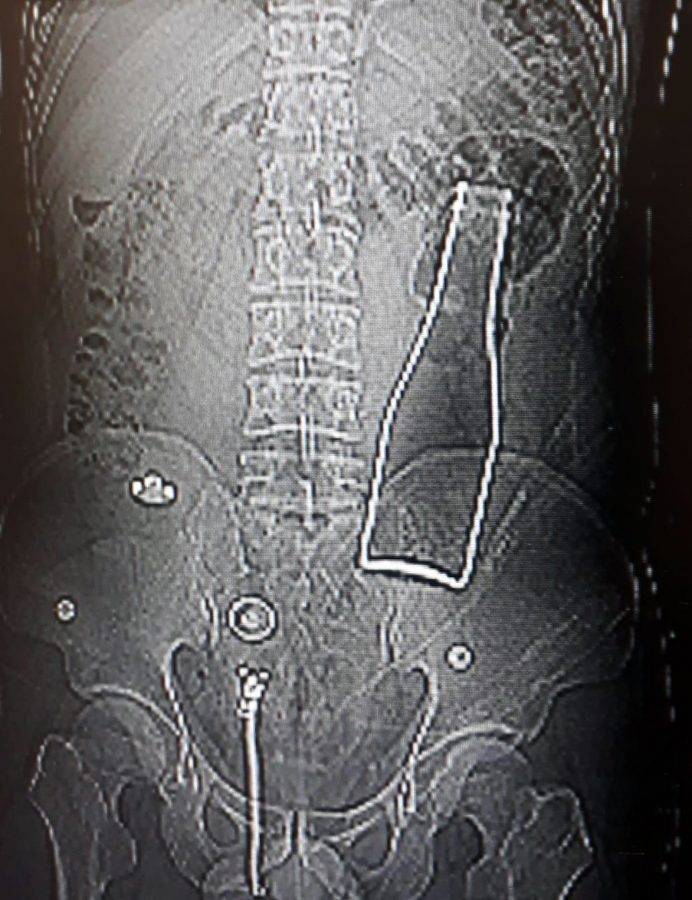

Dün akşam saatlerinde Karaman Eğitim ve Araştırma Hastanesi'ne gelen A.E., doktorlara karın ağrısı şikayetinin olduğunu söyledi. Çekilen röntgen filminde A.E.'nin kalın bağırsağının bulunduğu bölgede şişe olduğu tespit edildi. A.E.'nin makatından sokulduğu belirlenen soda şişesi, yaklaşık 1 saat süren ameliyatla çıkarıldı.